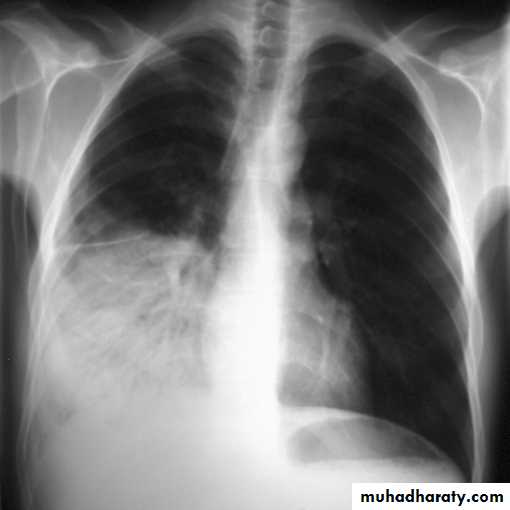

• Pleural effusion : collection of fluid within the pleural space. This can be further divided into Transudate , exudate, according to protein content .Other type of fluid collection within pleural space are

• Chest x-rays are the most commonly used examination to assess for presence of a pleural effusion, however it should be noted that on a routine erect frontal chest x-ray as much as 200-500 ml of fluid is

• required before it becomes evident .

blunting of the costophrenic angle

blunting of the cardiophrenic angle

fluid within the horizontal or oblique fissures

eventually a meniscus will be seen, on frontal films seen laterally and gently sloping medially

with large volume effusions, mediastinal shift occurs away from the effusion

• Lateral films are able to identify a smaller amount of fluid ( about75%)as the costophrenic angles are deepest posteriorly posteriorly

Pleura effusion signs

Obliteration of costo-pherinic anglesMeniscus sign

Lenticular sign